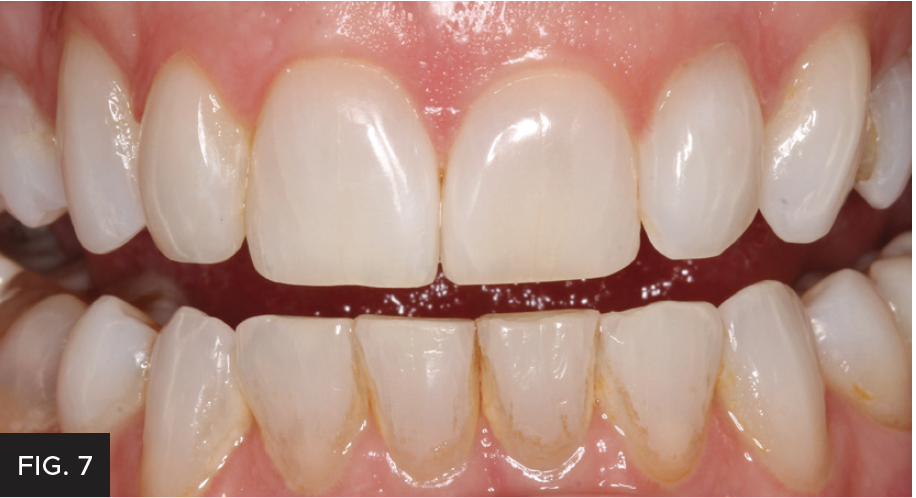

Each layer of composite material and tints were cured with a high-power curing light. For the final curing, glycerin was placed on the restoration’s surface to remove the oxygen inhibited layer; this hardened the surface and made it easier to achieve a beautiful polish. (FIG 7)

The post-operative right 1:1 view shows how all the characterizations make such a life-like restoration that blends the restoration into the tooth and the dental arch.